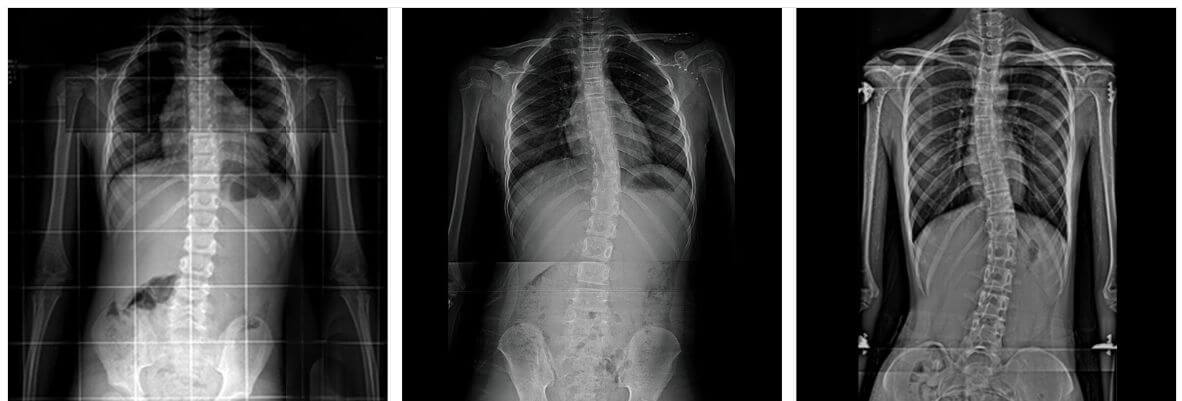

우리가 흔히 척추측만증으로 부르는 척추옆굽음증은 척추의 형태가 앞, 뒤, 좌, 우 혹은 복합형으로 틀어지고 휘어진 형태를 말합니다.

X-ray검사를 하면 척추뼈의 기형을 비교적 쉽게 발견할 수 있습니다.

측만증의 심한 정도는 각도로 표시하며, 이 각도의 정확한 명칭은 콥스각(Cobb's angle)이라 합니다. 이 각도가 몇 도인지 알아야 치료를 결정할 수 있습니다.

보통 척추가 10도 이내로 휘었을 때는 측만증이라 하지 않는데, 이는 일시적인 통증이 오거나 측만증이 없는 상태에서도 척추가 보통 10도 정도 휠 수 있기 때문입니다.

25도가 넘으로면 외관상의 변화가 나타나고, 45도 이상이면 수술적 치료대상이 됩니다.

척추 수술은 다양한 금속 내 고정 물을 통해 척추의 휘어짐을 최대한 교정한 뒤 척추 융합술을 통해 교정을 유지합니다.